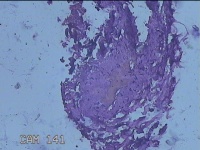

外阴部肿物

性别

男

年龄

29岁

临床诊断

皮脂腺囊肿(外阴部)

无

标本名称

大体所见

灰白暗红色肿物1.3x0.8x0.3cm一个,表面糜烂,切开肿物呈实性,切面灰白暗红色,质软。